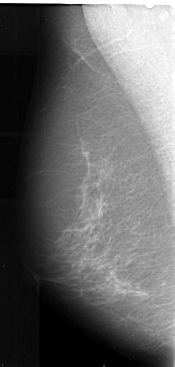

A_1021_1.LEFT_MLO

A_1021_1.LEFT_CC

LEFT_CC LINES 5401 PIXELS_PER_LINE 2641 BITS_PER_PIXEL 16 RESOLUTION 42 NON_OVERLAY

LEFT_MLO LINES 5491 PIXELS_PER_LINE 2611 BITS_PER_PIXEL 16 RESOLUTION 42 NON_OVERLAY